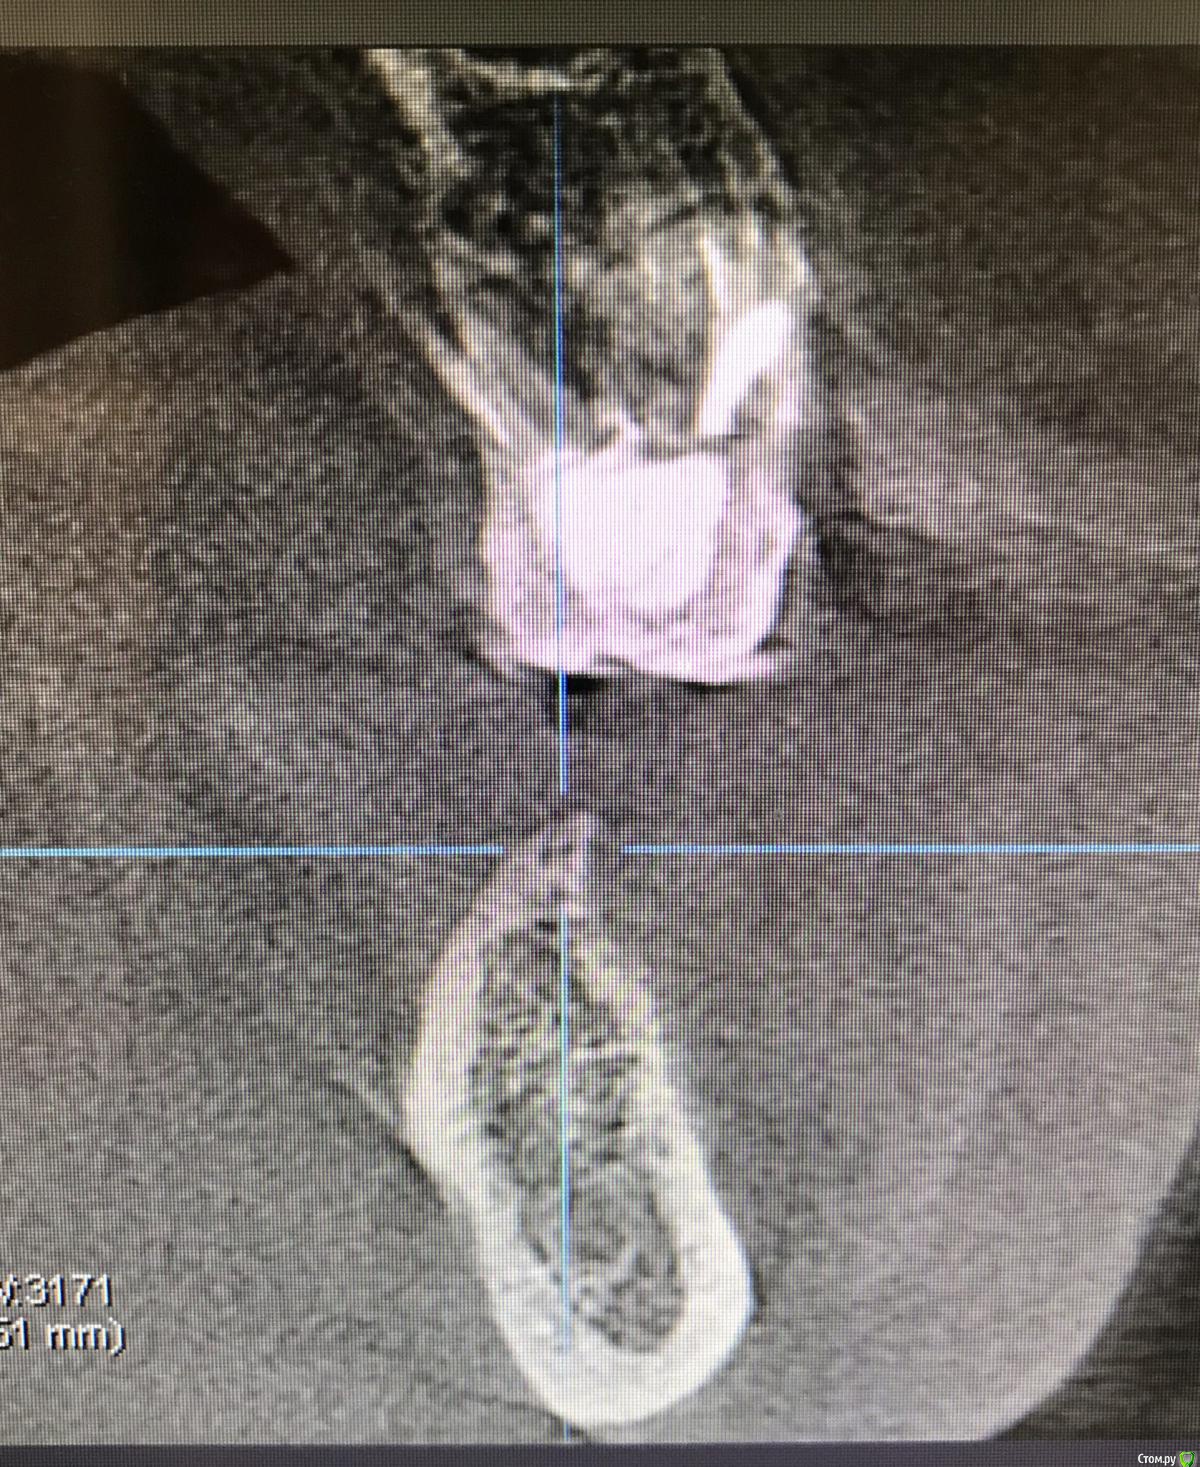

колесников Опубликовано 16 декабря, 2018 Автор Поделиться Опубликовано 16 декабря, 2018 (изменено) Поставлена задача:возместить дефект зубного ряда. Бюджет ограничен. Как видно по кт,для имплантации нет сложностей. Импланты Астра 4.0,поставлены с заглублением в оптимальной позиции. Дефицит прикреплённой слизистой вестибулярно у шеек имплантов возмещён роллом с гребня. Можно было этим ограничится. Однако при протезировании дефицит объема тканей будет очевиден. Роллы фиксированы к подвижной и тонкой слизистой,результат сомнительный,тк нет стабильности. Щечный тяж и скат гребня неминуемо приведут к рецесси слизистой у шеек имплантов. Можно было восстановить объём гребня при помощи нкр,затем лоскут с неба ( 1 год лечения). Или хотябы подсадить сст пожирнее.а потом асл (6мес),на первое время хватило бы. Но . Бюджет ограничен. Сроки тоже. Слово «костная пластика» вызывает панику. Новая задача: минимизировать вмешательства,убрать тяжи,создать объём,небо не трогаем. Проводим тоннельный графтинг. Получаем объём,поднимаем ткани и тяжи не тянут. Роллы получают покой ,стабильность и созревают в кратчайшие сроки. Графт поднадкостнично. Графт стабилен. Графт пропитался кровью,графт созревает. Результат быстрый. Дискомфорта 0. Затраты минимальные. Срок жизни такой пластики ни чем отличается от любой другой,в конечном итоге тает все. Если не стимулировать. Изменено 16 декабря, 2018 пользователем колесников 1 Ссылка на комментарий